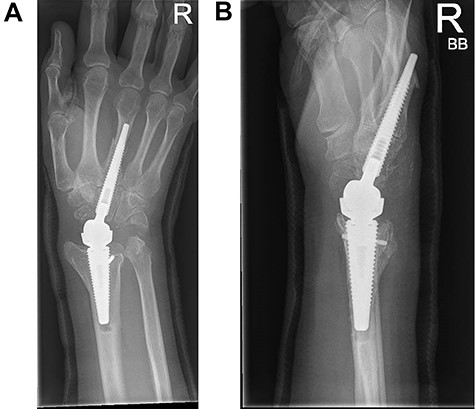

Following appropriate consultation and consent, she underwent total wrist arthroplasty. She reported complete pain relief and an improved range of movement. Ten weeks following surgery the patient presented in the emergency department following a fall. She landed heavily on the dorsiflexed hand and wrist, immediately noticing a change. Imaging confirmed that she had sustained a periprosthetic fracture in the middle finger metacarpal with dorsal displacement of the implant (Fig. 2A and B). Following a trial of non-operative treatment, she underwent revision surgery. The distal metacarpal implant was removed and replaced with a longer implant and the metacarpal fracture defect region was reinforced with autologous bone graft (Fig. 3A and B).

(A and B) PA and lateral radiographs showing a periprosthetic fracture around the metacarpal implant of a Motec wrist replacement.